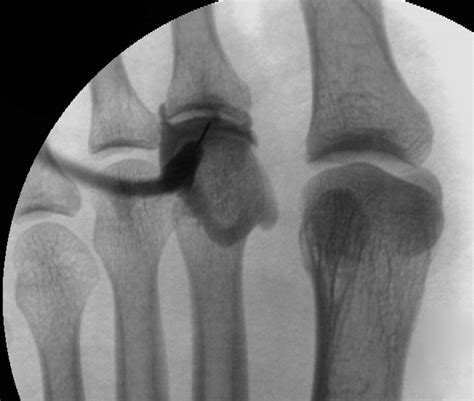

• Sesamoiditis: The sesamoid bones are small bones embedded within the tendons of the big toe. Inflammation of these bones, known as sesamoiditis, can cause pain and discomfort in the 1st MTP joint.

• Turf Toe: This injury occurs when the big toe is hyperextended, often due to sudden stops or changes in direction. It can cause significant pain and swelling in the 1st MTP joint.

Diagnosing problems with the 1st MTP joint typically involves a combination of physical examination, medical history, and imaging tests. A healthcare professional will assess the joint's range of motion, tenderness, and any visible deformities. Imaging tests such as X-rays, MRI, or CT scans may be used to get a clearer picture of the joint's structure and identify any underlying issues.

Imaging tests provide detailed views of the joint and surrounding structures. X-rays can show bone abnormalities, while MRI and CT scans offer more detailed images of soft tissues, ligaments, and tendons.